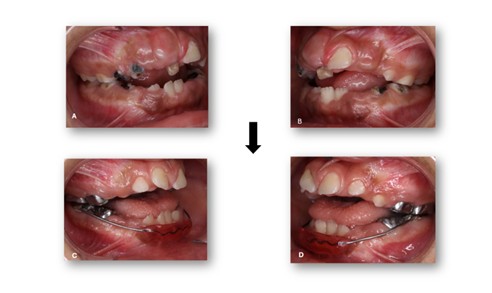

Figure 4: Pre- and post-operative records. A) Pre-operative intraoral view showing extensive caries and severe breakdown of tooth structure. B) Post-operative view demonstrating gingival exposure of the anterior teeth and improved oral condition following treatment.

Figure 5: Pre- and Post-Operative Records. Intraoral lateral views. A, B) Pre-operative views showing severe caries and tooth structure breakdown. C, D) Post-operative views showing restored teeth and improved occlusal condition.